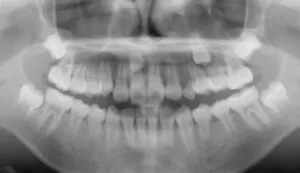

また、歯全体やあごの骨を写すパノラマ写真で全体像を見ると、乳歯や永久歯の状態もわかります。

乳歯から永久歯に生え変わる際に、永久歯が生まれつき足りない「欠損歯」や、余分な歯である「過剰歯」なども分かり、

こちらもとても大切な検査です。

最近歯科矯正を始めた我が家の娘に、なかなか抜けない乳歯があるな・・と思っていたら、本来生えてくるべき歯の隣の歯の上に永久歯が💧

さらに過剰歯があることもパノラマ写真でわかりました💦